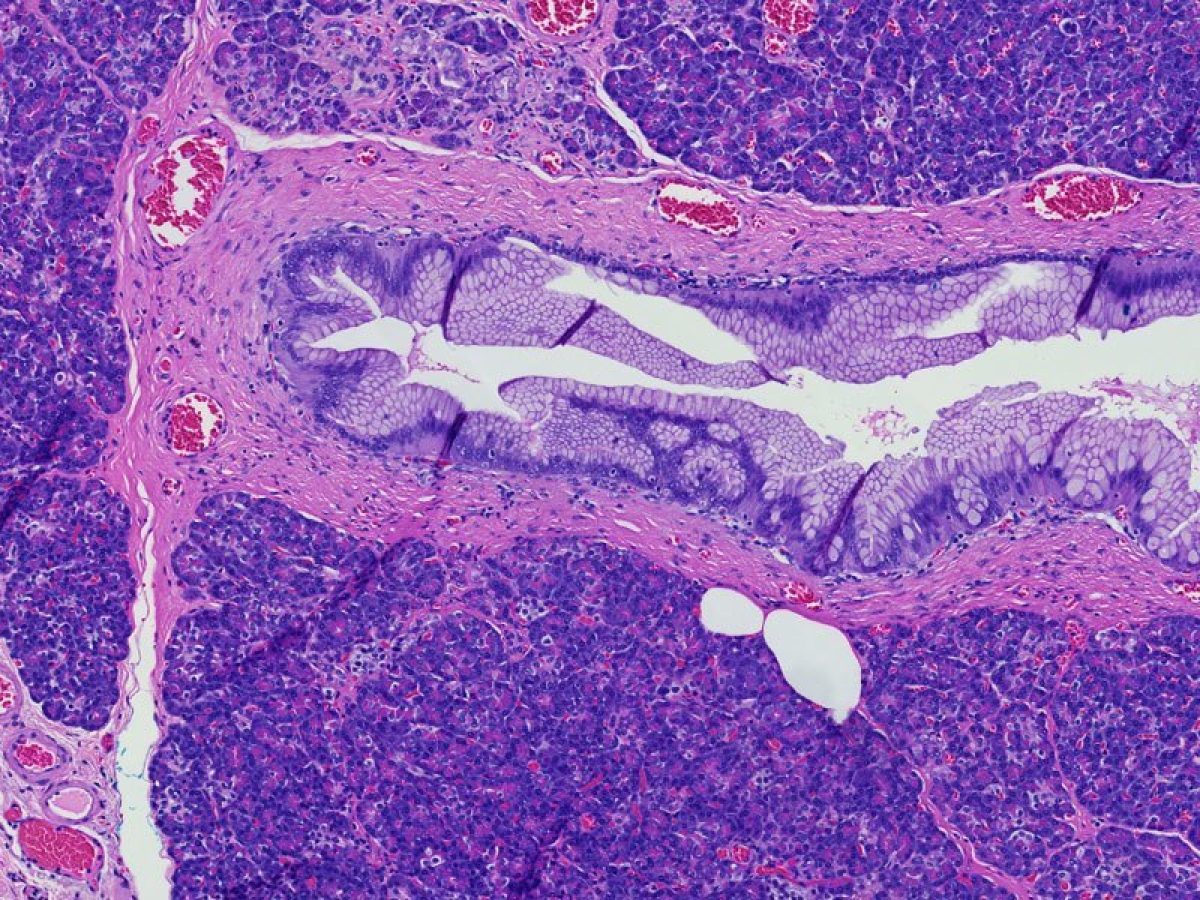

The form of cancer that most people are talking about when they refer to "cancer of the pancreas." These tumors account for 75% of all pancreas cancers.

Microscopically, adenocarcinomas form glands. These tumors can grow large enough to invade nerves which can cause back pain. They also frequently spread (metastasize) to the liver or lymph nodes. If this happens the tumor may be considered unresectable.